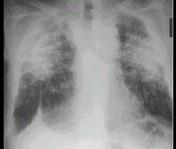

问题 男,52岁,从事矿井工作32年,近几年出现气喘,呼吸困难,X光片如图,其最可能的诊断为 ( )

选项 A.双肺浸润性结核 B.双肺真菌感染 C.两肺弥漫性间质性肺炎 D.两肺弥漫性纤维化 E.硅沉着病病

答案 E